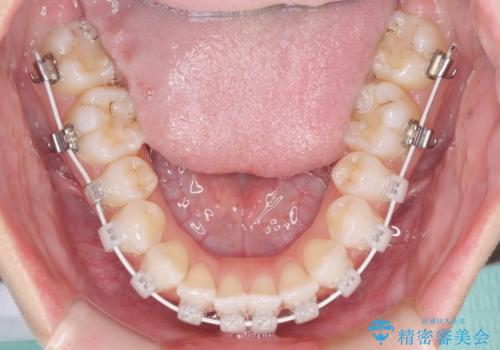

- 矯正装置

- 審美装置

- 海外留学を前に上下のデコボコと奥歯の咬み合わせを改善したいとのことで来院された患者様です。

期間が限られていたため、ワイヤー装置による矯正治療を行うこととしました。

治療開始から4ヶ月ほどで概ね歯列が整い、その後の3ヶ月で細かい部分を仕上げていきました。